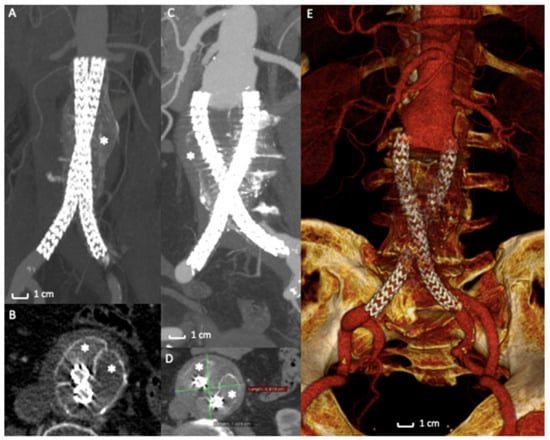

Figure 4. Case of Nellix Endograft Failure due to distal migration. (A) Computed Tomography Angiography detail of a Nellix endograft implantation. The asterisk (*) indicates the polymer filled endobags that correctly seal the aneurysm sac. (B) Axial view of the same exam highlights the correct stents’ and endobags’ configuration, asterisks (*) mark the two endobags adapted to the aneurysm sac. (C) Computed Tomography Angiography detail of the 2-year follow-up exam revealing a distal migration of the entire system (arrows) with AAA enlargement (D) and endobags dislocation (*). (E) 3D volume rendering of Computed Tomography Angiography of the endograft migration and failure, requiring open surgical conversion.

In a retrospective analysis [66] of prospectively collected data of 295 cases of endovascular aneurysm sealing using the Nellix device for abdominal aortic aneurysm, therapeutic failure was seen at a surprising and alarming rate of 33.2%. The most common failure mechanism was the stent graft migration associated with type IA endoleak and sac expansion, as demonstrated by a recent systematic review (Figure 4A–E) [58]. In several cases of failure, stent grafts were explanted from the patients’ bodies with a significant open vascular intervention. EVAS failures were also responsible for AAA rupture with severe or fatal consequences for the patients. In case of graft explantation, surgeons noted that the bags containing polymer were still intact, the polymer was not leaking into the vasculature, and maintained the expected consistency. The cause of failure was reported to be the lack of a stable proximal fixation of the entire device into the aneurysm sac [67,68,69].